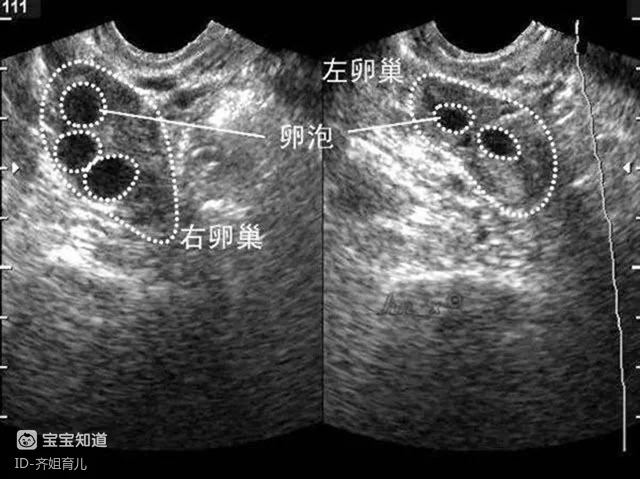

促排卵的过程根据每个人体质的不同可能要持续一到两周,主要是注射两种促性腺激素来加速卵泡的成熟。

在这个过程中,要通过B超监测卵泡的成熟情况,当卵泡发育到18毫米以上就可以了。